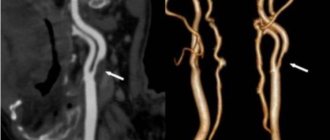

Diagnostics

If poor patency of arteries and veins is suspected, the following studies are performed:

• Cholesterol analysis.

• Chest X-ray.

• CT scan.

• Ultrasound.

• Echocardiogram.

• ECG.

• MRI scan.

• Angiogram.

Magnetic resonance imaging (MRI) uses magnets and radio waves to produce images inside the body without a surgical incision. Unlike CT scans, MRIs do not use ionizing radiation. This is considered a safer alternative.